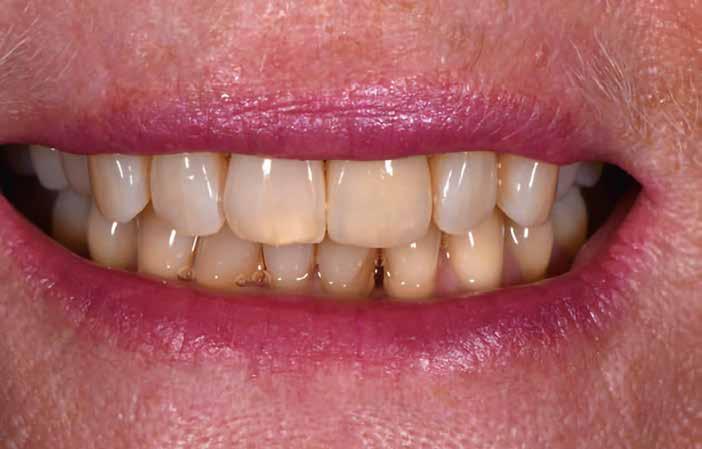

Próba és behelyezés

A felépítmény próbája és behelyezése a szájba a segédelemmel történik. Az emergenciaprofil kezdetben még

enyhén anémiás (vérszegény – a ford.), de gyorsan újra telítődik, tökéletesen illeszkedve a szituációhoz (36–42. képek)

A páciens a DD cube One koronát választotta, ami szín és transzparencia szempontjából is nagyon harmonikusan illeszkedett a teljes képhez (43–44. képek)

36–37. képek: A DD Bio ZW iso korona a mintán és in situ.

38–39. képek: A DD cube One korona a mintán és in situ.